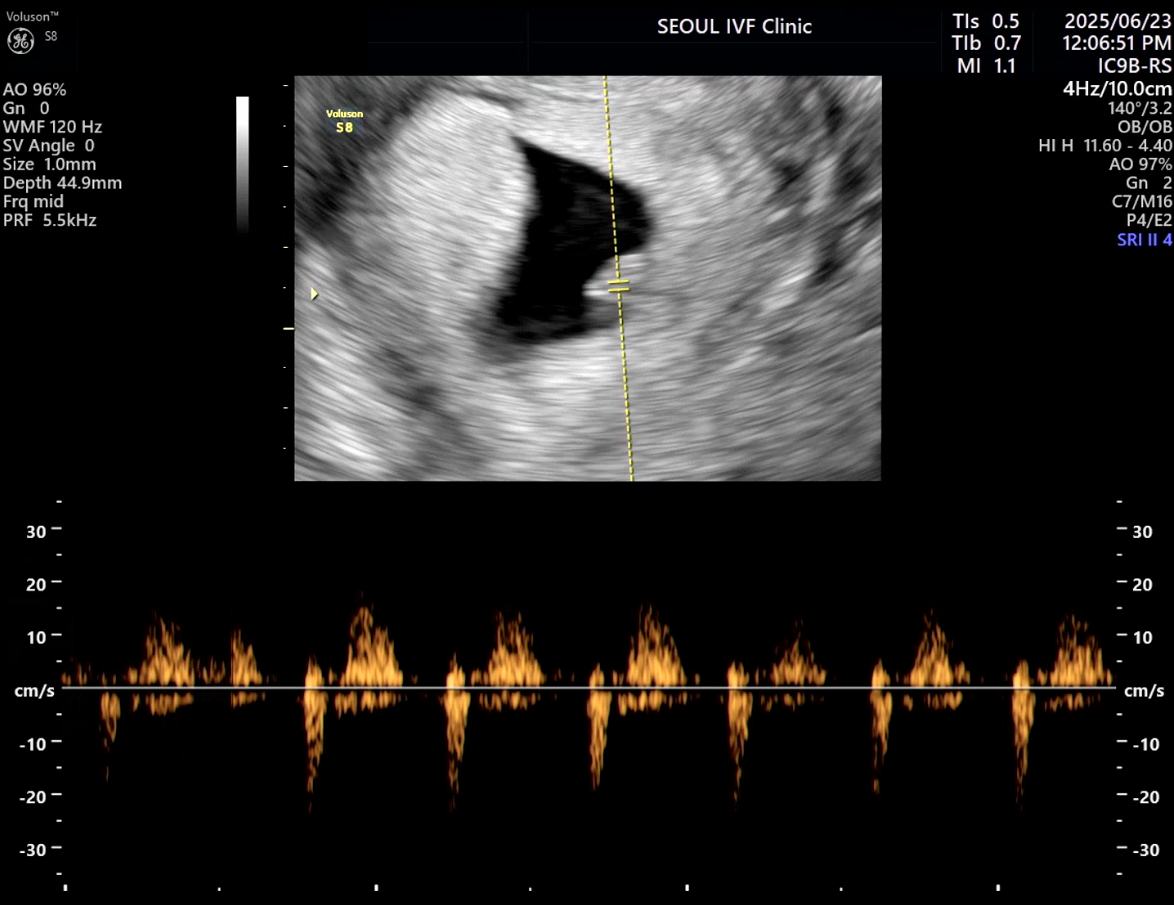

| 가슴 떨리는 임신 이야기를 공유해 주세요. | 몇 번의 실패로 절망적인 순간들을 겪었지만, 마침내 임신테스트기에 두 줄이 나온 순간은 지금도 잊을 수 없습니다. 특히 인공수정 1차에서 약간의 수치가 보여 잠시 기대했지만, 화학적 유산으로 끝나며 큰 좌절을 겪었습니다. 그러나 곧바로 이어진 시험관 1차에서 임신이 확인되었을 때, 그 기쁨은 말로 표현할 수 없을 만큼 벅찼습니다. |

| 치료 도중 느꼈던 가장 기뻤던 순간과 절망적인 것들은 무엇인가요? 잊지 못할 경험이 있나요? | 가장 기뻤던 순간은 역시 시험관 1차에서 임신이 확인되던 날이었습니다. 그날의 설렘과 감동은 평생 잊히지 않을 것 같습니다. 가장 절망적이었던 경험은 인공수정 1차에서 화학적 유산 판정을 받았을 때였습니다. 잠시나마 희망을 가졌던 만큼 무너지는 마음이 컸지만, 포기하지 않고 다시 도전했기에 결국 기적 같은 결과를 만날 수 있었습니다. |

| 서울IVF여성의원의 난임 치료에 대해 말씀해 주실 것이 있나요? | 난임 전문 병원답게, 환자의 입장을 깊이 이해해주고 세심하게 배려해 주신 점이 무엇보다 좋았습니다. 이유정 원장님과 의료진의 진심 어린 태도 덕분에 힘든 과정을 견뎌낼 수 있었고, 믿고 치료에 임할 수 있었습니다. |